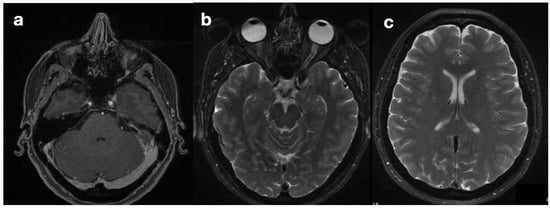

She was diagnosed with idiopathic intracranial hypertension (IIH) based on a highly suggestive clinical presentation (chronic and drug-resistant cephalgia and progressive visual loss with no alternative explanation). MRI, performed upon the patient’s admission (Figure 1), showed asymmetry of the transverse sinuses, suggesting incomplete stenosis (a), mild turgidity of the optic nerve sheath (b), and normal ventricles (c). Together, these findings strengthened the suspicion of IIH [1,2]; therefore, the patient was referred for neurosurgical treatment. Placement of a ventriculoperitoneal shunt (VPS) (Hakim Codman programmable valve, initial valve-opening pressure of 140 cmH2O) revealed intracranial hypertension and led to symptom relief. Normal CSF composition and the absence of localizing signs or intracranial masses confirmed the diagnosis of IIH according to modified Dandy’s criteria [3].

Figure 1. Preoperative MRI. Images showing the findings of the asymmetry of transverse sinuses (a), optic nerve sheath enlargement (b), and normal ventricles (c), compatible with intra-cranial hypertension.